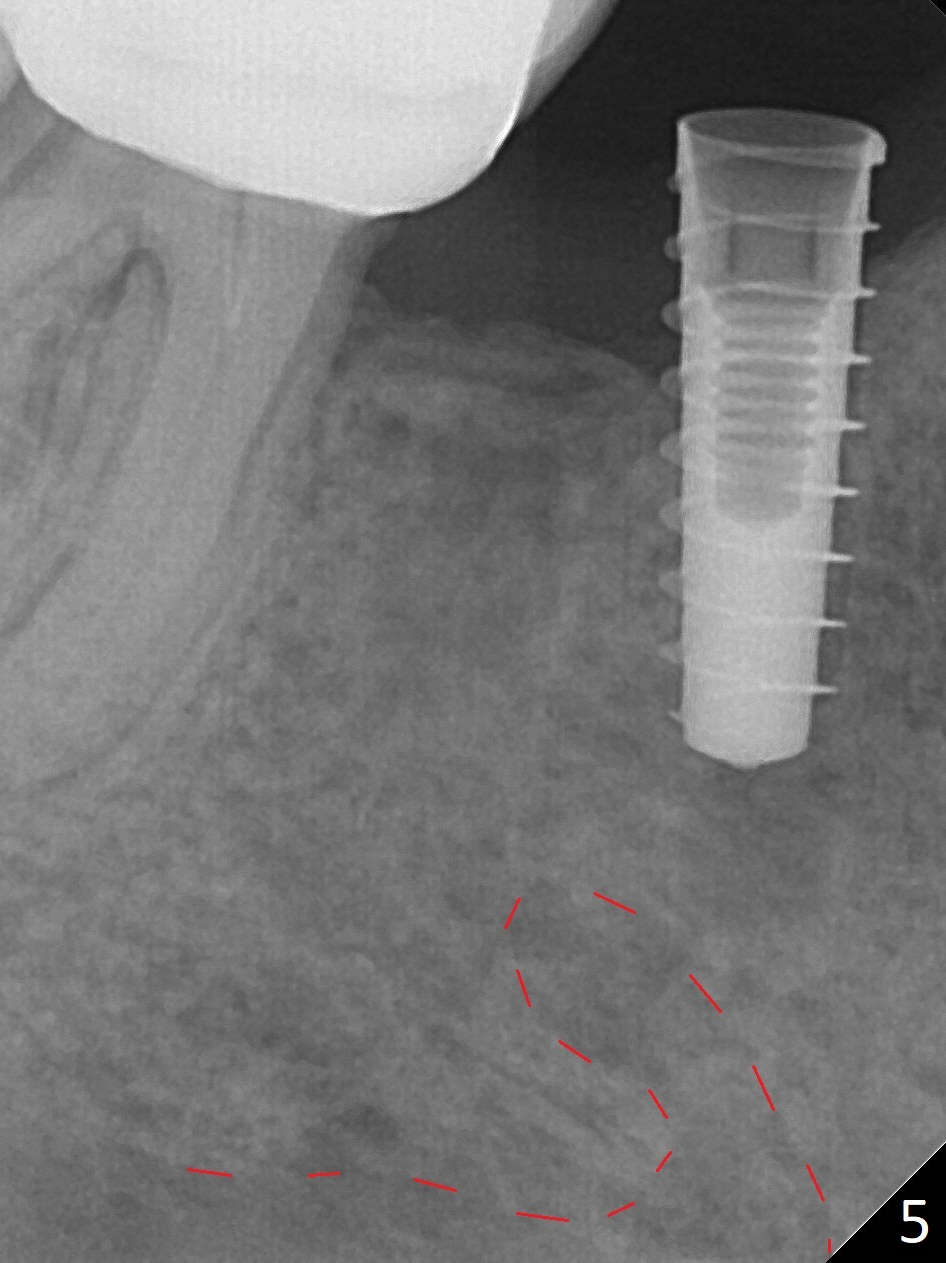

The patient returns for implant placement 11 months post extraction of #28 and 29. With flapless manner, initial osteotomy happens to drop into the original socket of #28 (Fig.4). After use of 3.3 mm Magic Drill (MD) and Final Drill for 15 mm, a 4x11 mm dummy implant is placed (Fig.5). It appears that the implant is long for the site (red dashed line: Mental Loop). However, a definitive implant (4x9 mm, IBS) has difficulty to reach its depth (Fig.6). After several rounds of untorque and retorque, the implant does not seat completely (Fig.7, implant driver disengagement) with autogenous bone placed distal (>). Retrospectively, a larger MD should have been used (3.8 mm) for complete seating in the dense bone. In fact she is post breast cancer treatment with 50% chance of relapse. The patient returns for follow up 1.5 months postop (Fig.8). The wound has healed. Impression is taken 5 months postop (Fig.9). When the crown is cemented, food impaction is an issue between the implant crown and crown at #30. Since the tooth #30 is mesially tilted with distal open margin and apical infection, the tooth will be extracted. Osteotomy is going to be initiated in the mesial slope of the mesial socket (Fig.9 red line). An implant will be placed more or less in the mesial socket (green box).